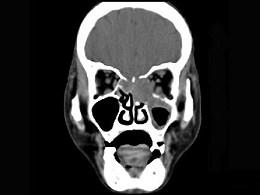

问题 男性50岁,涕中带血半年,体检发现右侧颈部多个硬结,CT扫描如图所示,请选择正确的描述和结论 ( )

选项 A、考虑为右侧筛窦黏液性囊肿 B、考虑为右侧筛窦癌 C、软组织影累及对侧筛窦、右侧上颌窦 D、右侧眶内壁、上颌窦壁及颅底骨质破坏 E、右侧筛窦内见软组织块影,边缘不规则

答案 BCDE